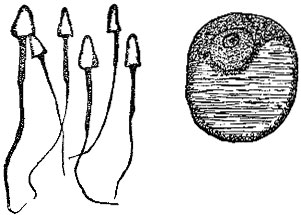

The Male Elements.—The spermatozoa are exceedingly delicate and minute; they constitute the greatest part of the semen, or sperm. They are peculiar shaped bodies, having a head, body, and tail, as illustrated in the accompanying figure, and they can only be seen by powerful magnifying glasses. (Fig. 1.)

They have the remarkable property of moving about with considerable activity, and their number is almost beyond computation.

Only One Male Element Necessary.—Although this number is so vast, yet only a single one is required to endow the female cell, or egg, with life. It is another illustration of how nature does everything possible to increase the chances of perpetuating the race, for without such immense numbers, the chances of the female egg being fertilized would be much less.

[Pg 7]The Female Element.—As I have already said, the female germ-cell is also known as the ovum, or egg. A single ovum is shown in Fig. 1.

One Female Element; Many Male Elements.—The human ovum is often said to be a miniature of the egg of the common fowl, although there are some quite marked differences between the two. It is a very interesting fact to note that there is only one egg given off at a time; while there are many thousands of the male elements. This is in harmony with the larger size of the egg, and the fact that while this egg awaits fertilization it is most carefully protected within the body of the mother.